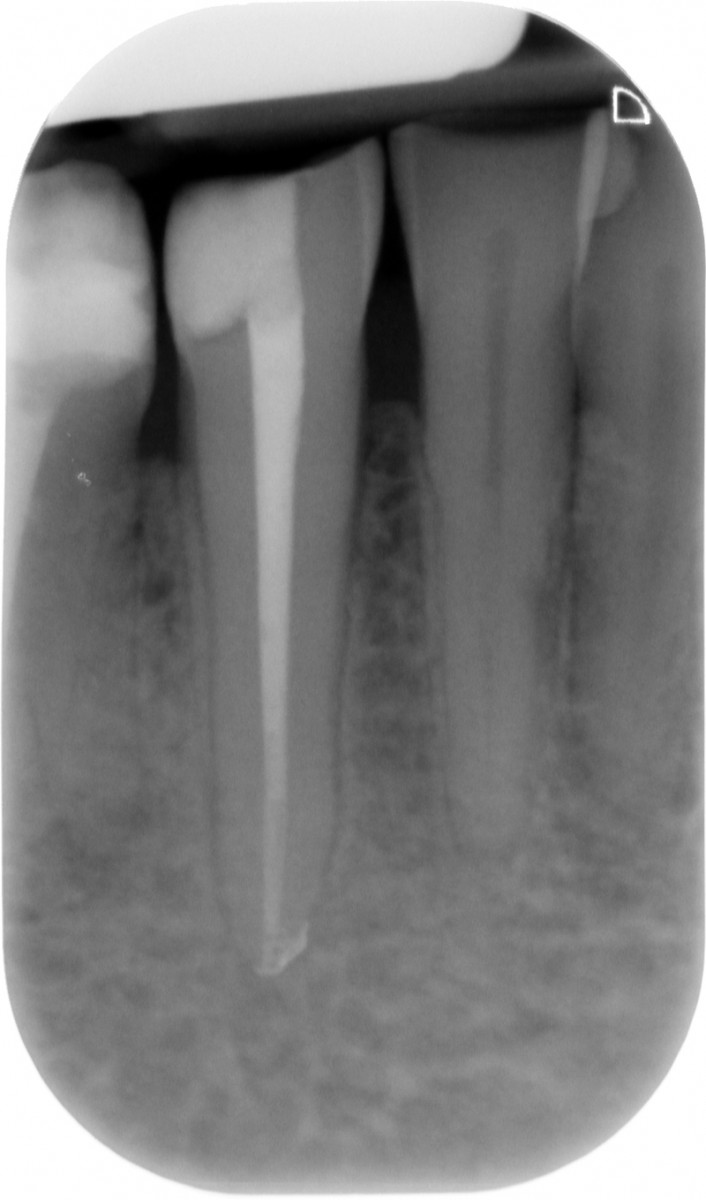

The gutta-percha point inserted into the root canal properly, adapting it to a size almost equal to the one employed to shape the apical terminus. Not wider, not smaller. Here are exposed a couple of cases made by shaping the root canal with a NiTi instrumentation technique and followed up for 9 to 12 months (Fig. 1-6).

It’s encouraging its easy handling and quite precise adaptation to the apical part of the root canal. The periapical healing, assessed by 2D-Rx, is considered satisfactory but further analysis and clinical studies related to these particular cements should be performed to confirm the first encouraging results.